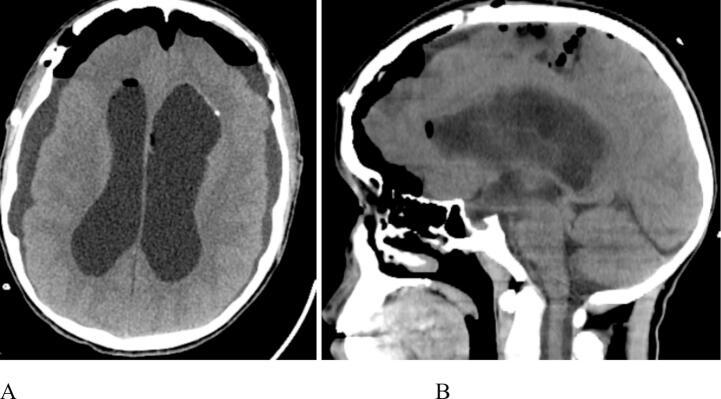

Epidermoid cysts are benign inclusion cysts that arise from ectopically displaced ectodermal tissue. Intraventricular epidermoid cysts are uncommon, and involvement of the bilateral lateral ventricles is rarely reported. Computed tomography (CT) scans typically show well-localized, hypodense lesions. These cysts are slightly hyperintense to cerebrospinal fluid (CSF) on both T1 and T2 magnetic resonance imaging (MRI) sequences.

表皮样囊肿是由异位的外胚层组织形成的良性包涵囊肿。脑室内表皮样囊肿并不常见,双侧侧脑室受累的情况鲜有报道。计算机断层扫描(CT)通常显示病变定位良好、密度减低。在T1和T2磁共振成像(MRI)序列上,这些囊肿相对于脑脊液(CSF)呈轻度高信号。

病例报告

我们报告一名17岁男性,因有四年发作性全身强直阵挛性癫痫和反复发作的搏动性全头痛病史,被诊断为双侧侧脑室表皮样囊肿。他接受了手术,组织病理学证实为表皮样囊肿。术后,患者症状有所改善。